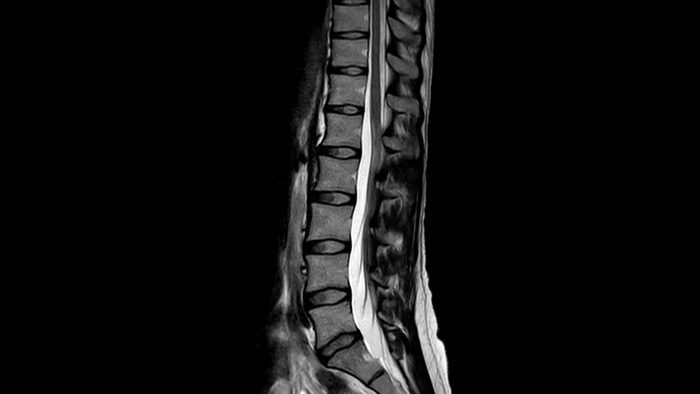

さらなる高速化の実現 MRI検査を最大65%高速化²、時間の有効活用が可能

確信が持てる画像診断 同じスキャン時間で、空間分解能を最大65%向上⁴

さらなる高速化の実現 SmartSpeedはAIの搭載と対応シーケンスの拡大により、MRI検査のニーズに応え、高速かつ高画質イメージングを提供します。

確信が持てる画像診断 すべての臨床領域でイメージング機能を拡張します。医療従事者が享受できるメリットをご覧ください。

1 稀なケースとして、マグネットの密封が損なわれた場合でもヘリウムの量はわずかであるため、漏れたヘリウムが室内の酸素レベルに影響を与えることは実質的にありません。 2 Philips SENSEとの比較。 3 心拍数が低い (50 bpm) とき。Compressed SENSEなしのフィリップススキャンと比較した場合。 4 等方性3D MSK VIEWスキャンで、Compressed SENSEなしのフィリップススキャンと比較した場合。